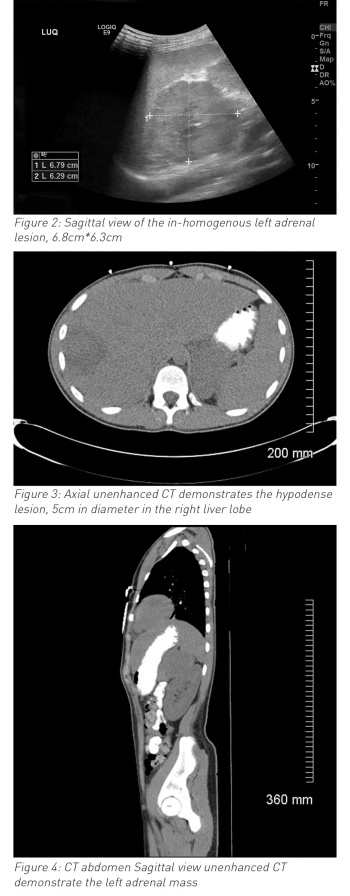

During his hospital stay it was noted that he had an episode of high blood pressure (140/90mmHg) and developed ventricular bigeminy and trigeminy (see ECG in Figure 1). Chest x-ray and echocardiography were normal. Ultrasound and MRI abdomen reported left side suprarenal mass (8cm) and associated liver abscess (7cm x 7cm x 7cm). Urine catecholamines were normal. Liver abscess (abscess grew Streptococcus intermedia) was treated with drainage and with six weeks antibiotics. Paraganglioma was surgically resected successfully three months after initial diagnosis and full evaluation (genetic testing and exclusion of MEN syndrome and von-Hipple-Lindau syndrome). Ventricular bigeminy resolved completely and final diagnosis of non-secreting pheochromocytoma and coincidental liver abscess (likely due to trauma in the past). He was discharged home after full recovery. He is being followed up with regular abdominal imaging; to date, no concerns have been reported.